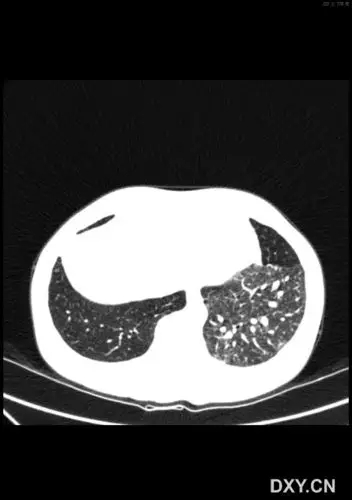

【影像读片】肺隔离症?